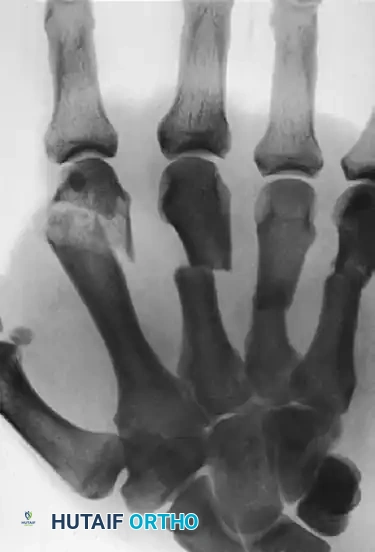

FIGURE 67-40 A: Preoperative radiograph demonstrating displaced, closed fractures of the metaphyseal shafts of the right middle, ring, and small digits, accompanied by a highly comminuted intraarticular fracture of the head and distal metaphysis of the index finger. This complex injury pattern results in profound instability and loss of the hand's architectural framework.

FIGURE 67-40 B: Postoperative radiograph demonstrating tubular plate fixation of the index, middle, ring, and small metacarpals. For the index finger, the plate acts as a neutralization/buttress plate, bridging the comminuted metaphyseal segment while securing the reconstructed articular head. (From Hastings H II: Unstable metacarpal and phalangeal fractures treatment with screws and plates, Clin Orthop Relat Res 214:37, 1987.)